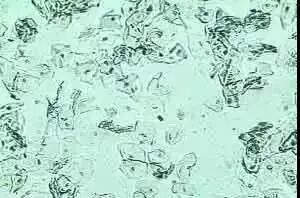

清洁度正常情况下阴道内有需氧菌与厌氧菌形成正常阴道菌群,其中阴道乳酸杆菌占优势阴道与这些菌群形成一种平衡状态阴道分泌物检验显示以杆菌为主,另外可有少量上皮细胞及白细胞当外来病原生物感染,机体免疫力低下,内分泌水平变化或其他某种因素破坏这种平衡就会引起感染,出现大量上皮细胞、白细胞,使阴道清洁度下降。

所以清洁度主要以白细胞、上皮细胞、阴道杆菌与杂菌的多少来划分1Ⅰ~Ⅱ度属正常Ⅲ~Ⅳ度为异常白带,表示阴道炎症,主要见于各种阴道炎如细菌性、霉菌性、滴虫性阴道炎,并同时可发现有关病原体;单纯清洁度改变常见于非特异性阴道炎,包括化脓性感染性阴道炎、嗜血杆菌性阴道炎、老年性或婴幼儿的阴道炎。

2阴道清洁度差还可见于:输卵管或子宫腔炎症、异物、赘生物、宫颈内管及宫颈的炎症或赘生物,阴道本身的创伤(如流产、产后因产道创伤所致)此外,正常女性在排卵前期清洁度好,在行经期和绝经期,清洁度差阴道清洁度镜检。

阴道清洁度是利用显微镜对阴道分泌物湿片和染色涂片检查,观察其清洁度和有无特殊细菌及细胞等,确认阴道清洁度,判断阴道有无炎症,还可以进一步诊断炎症的原因。

阴道清洁Ⅰ度:镜下以阴道杆菌为主,并可见大量上皮细胞。

阴道清洁Ⅱ度:有部分阴道杆菌及上皮细胞,部分白细胞和杂菌。

阴道清洁Ⅲ度:少量阴道杆菌和上皮细胞,大量白细胞和其他杂菌。提示炎症,如阴道炎宫颈炎。

阴道清洁Ⅳ度:镜下无阴道杆菌,几乎全是白细胞和大量杂菌多见于严重阴道炎,如淋球菌阴道炎、滴虫性阴道炎等白细胞在悬滴液中,正常白带高倍视野仅能看到一、二个白细胞,如存在大量白细胞应考虑滴虫病或宫颈炎;念珠菌病及细菌性阴道病白带的悬滴液涂片中白细胞少。